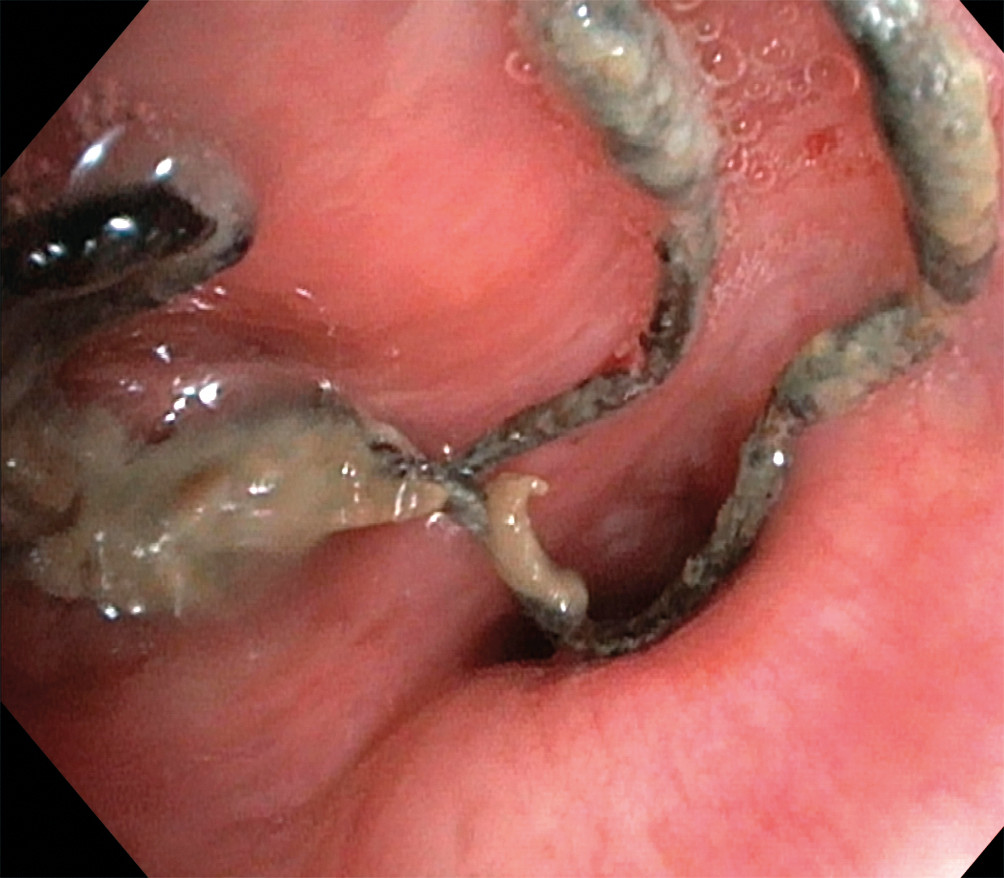

På bildet, tatt ved bronkoskopi, ses suturmateriale og purulent slim som ligger endobronkialt, nær ostiet for det apikale underlappssegment på høyre side.

Pasienten er en kvinne i 50-årene. Som barn ble hun operert med partiell høyresidig underlappsektomi. Man lot det apikale underlappssegmentet stå igjen, og det ble brukt ikke-resorberbar tråd. Etter operasjonen har hun hatt tilbakevendende nedre luftveisinfeksjoner, alt fra bronkitt til pneumoni. Forut for den aktuelle bronkoskopien ble det gjort CT thorax som avdekket abscessutvikling (CT-bilde). Ved utredning fant man ingen underliggende immunsvikt eller andre forklaringer på infeksjonstendensen. Hun røyker daglig, men har ingen obstruktiv lungesykdom. Suturmaterialet som ble avdekket ved bronkoskopi var i retrospekt synlig på CT thorax-bildet, men kunne muligens mistolkes som sekret i luftveiene.

Suturmateriale er som et fremmedlegeme og fremmer dannelse av en biofilm og bakteriekolonisering. Dette er høyst sannsynlig årsaken til gjentatte pneumonier og utviklingen av lungeabscess (1) . De synlige suturene lot seg fjerne med tang bronkoskopisk. Prosedyren ble gjort først etter at pasienten hadde gjennomført langvarig antibiotikabehandling. Selv om det hadde gått mer enn 40 år siden operasjonen fant sted, var ikke suturmaterialet brutt ned. I litteraturen har vi funnet bare få rapporter om fjerning av aspirert fremmedlegeme med tilsvarende tidsspenn fra aspirasjon til fjerning (2) . I disse tilfellene har indikasjonen for utredningen vært tilbakevendende pneumonier, slik som hos vår pasient. Det vi kan lære av kasuistikken, er at hos pasienter med gjentatte nedre luftveisinfeksjoner av ukjent årsak bør man vurdere CT thorax og bronkoskopi.